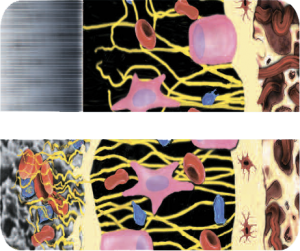

DISEÑO HÍBRIDO CONTEMPORÁNEO

Topografía de superficie híbrida contemporánea (gruesa y fina)

Micrométrica fina 2000 X

Superficie micrométrica fina:

En el cuello la superficie del implante es Osseotite® (grabado ácido doble), lo que permite una protección contra la periimplantitis. Tiene rugosidades micrométricas finas que van de 1 a 3 micras.

Micrométrica gruesa 2000 X

Superficie micrométrica gruesa:

En el cuerpo del implante existe una transición hacia una superficie más rugosa que favorece la oseointegración. Las rugosidades micrométricas gruesas en esta sección son mayores a 10 micras.